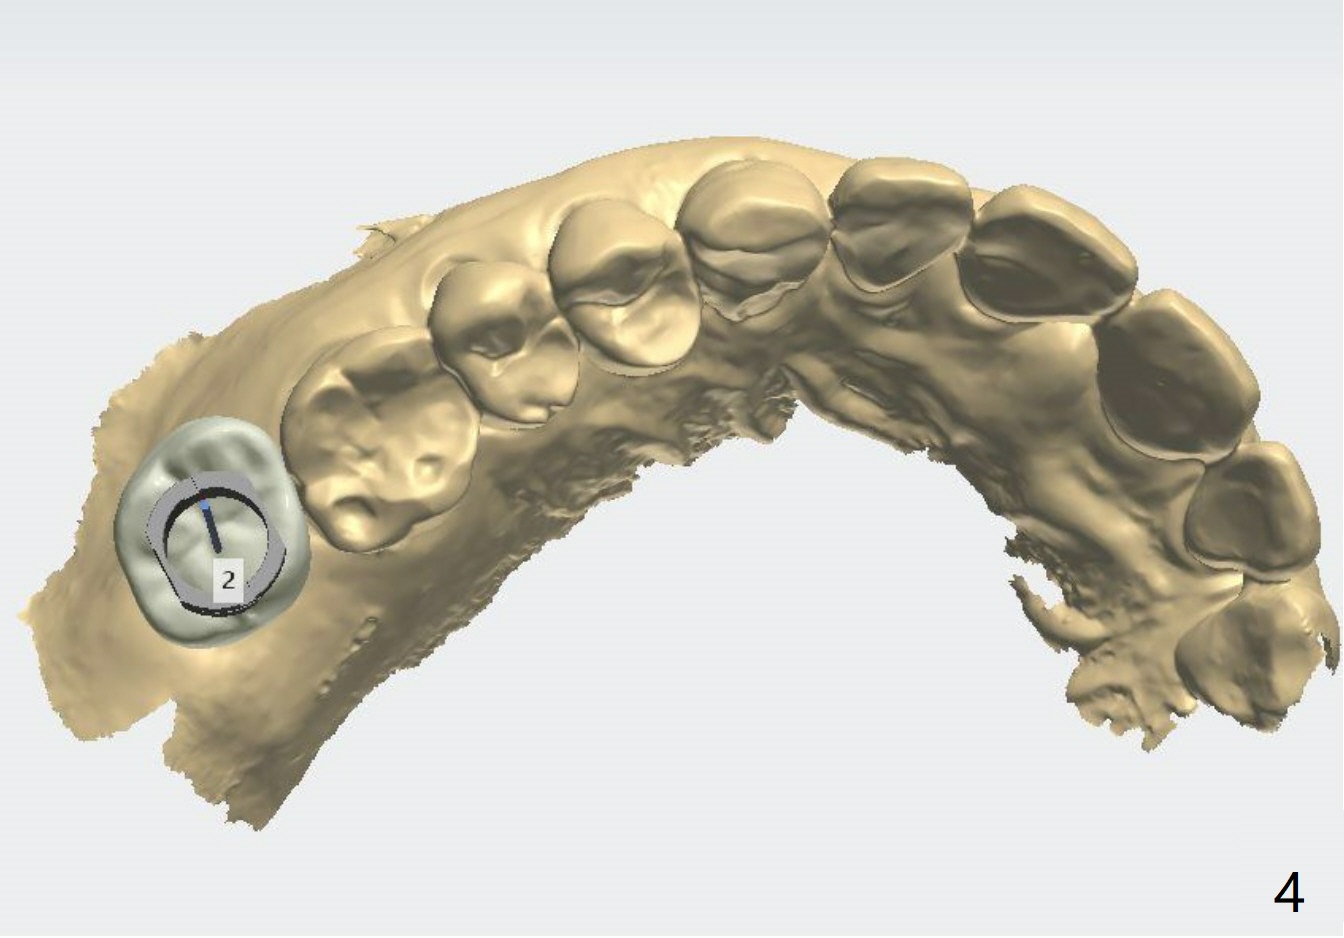

Short Fixture with Low Density

A 70-year-old woman